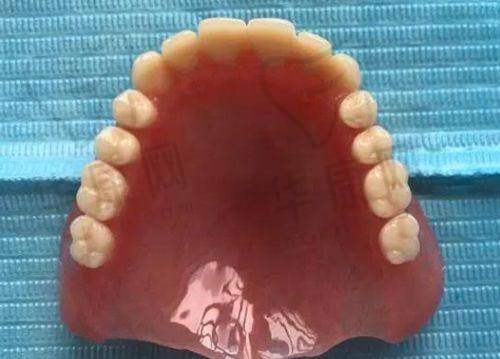

程勇医生擅长的项目十分广泛。在种植技术方面,他精通普通种植、即刻种植、微创种植、微创即刻种植、全口半口牙颌种植等。同时,他还掌握穿颧穿翼种植技术、all - on - 4即刻负重种植技术等多种精良种植技术。在疑难种植治疗方面,他能够处理全口种植义齿、前牙美学种植、骨量不足的种植治疗等各类疑难种植病例。此外,他还擅长侧壁开窗上颌窦底提升手术、自体骨移植手术等其他手术以及种植义齿修复、吸附性全口活动义齿修复等。